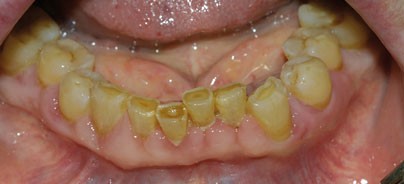

Die Anamnese ergab eine parodontale Vorbehandlung vor circa zehn Jahren. Der letzte Zahnarztbesuch lag ungefähr ein Jahr zurück. Damals seien keine Veränderungen festgestellt worden. Im weiteren Gespräch wurde die Patientin zu Allgemeinerkrankungen und verordneten Medikamenten befragt. Laut Angaben der Patientin litt sie unter Bluthochdruck und einer Herzinsuffizienz. Sie nahm die in Tabelle 1 aufgeführten Medikamente ein. Dabei sei während eines Krankenhausbesuches vor vier Monaten das Präparat Amlodipin erstmalig verordnet worden. Die Angaben wurden später durch Rücksprache mit der behandelnden Hausärztin verifiziert. Bei der klinischen Untersuchung zeigten sich generalisierte Gingivahyperplasien an allen Parodontien des Ober- und Unterkiefers (Abb. 1 und 2). Es lag eine generalisierte Gingivitis und plaqueinduzierte Parodontitis marginalis chronica vor, die durch die vorhandenen Pseudotaschen noch verstärkt wurde. Die geröteten und ödematös geschwollenen Pseudotaschen überlagerten partiell die Zahnkronen interdental, sodass traumatische Einbisse bei Interkuspidation bestanden. Teilweise entleerte sich Pus über die Pseudotaschen. Das angefertigte Orthopantomogramm bestätigte einen vertikalen und horizontalen Knochenabbau, ausgelöst durch die parodontale Vorerkrankung. Es wurde die klinische Verdachtsdiagnose einer Amlodipin-induzierten Gingivahyperplasie bei generalisierter Parodontitis marginalis chronica gestellt. Aufgrund des Alters der Patientin und der bestehenden Vorerkrankungen wurde ein minimalinvasives Vorgehen favorisiert. Dazu wurde eine vorsichtige Entfernung des vorhandenen Zahnsteins vorgenommen. Die Pseudotaschen wurden mit Chlorhexidinlösung gespült und der Patientin die Anwendung von Chlorhexidinlösung zur Mundspülung verordnet. In einer zweiten Sitzung wurde zu differenzialdiagnostischen Zwecken eine Probeexzision im Unterkiefer-Prämolarenbereich rechts durchgeführt. Das histologische Ergebnis bestätigte das Vorliegen einer Gingivahyperplasie. Nach Rücksprache mit der behandelnden Hausärztin konnte ein Absetzen der Medikation von Amlodipin vorgenommen werden. Die Patientin wurde nach einem und drei Monaten nachkontrolliert. In diesem Zeitraum kam es zu einer Reduktion der Hyperplasie und subjektiv deutlicher Beschwerdebesserung. Es lagen deutlich reizlosere gingivale Verhältnisse im Vergleich zur Erstuntersuchung vor (Abb. 3 und 4). Eine Parodontalbehandlung wurde empfohlen. Zusätzlich vorliegende Ödeme der unteren Extremitäten hatten sich ebenfalls zurückgebildet.